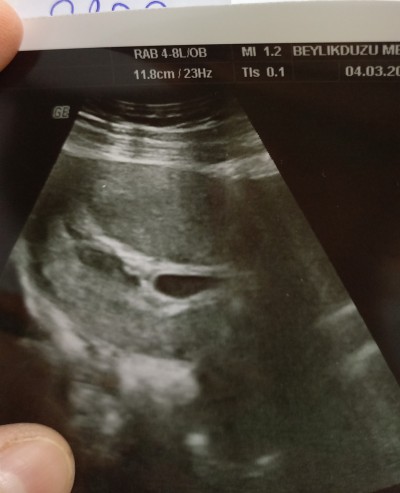

Merhabalar hafif kanama şikayetiyle dr gittim kese etrafında kanama olduğunu söyledi dr kese assagiya yerleşmis cokta saglikli kese degil dedi aranızda boyle olan varmi sonradan düzelen 6+1

image